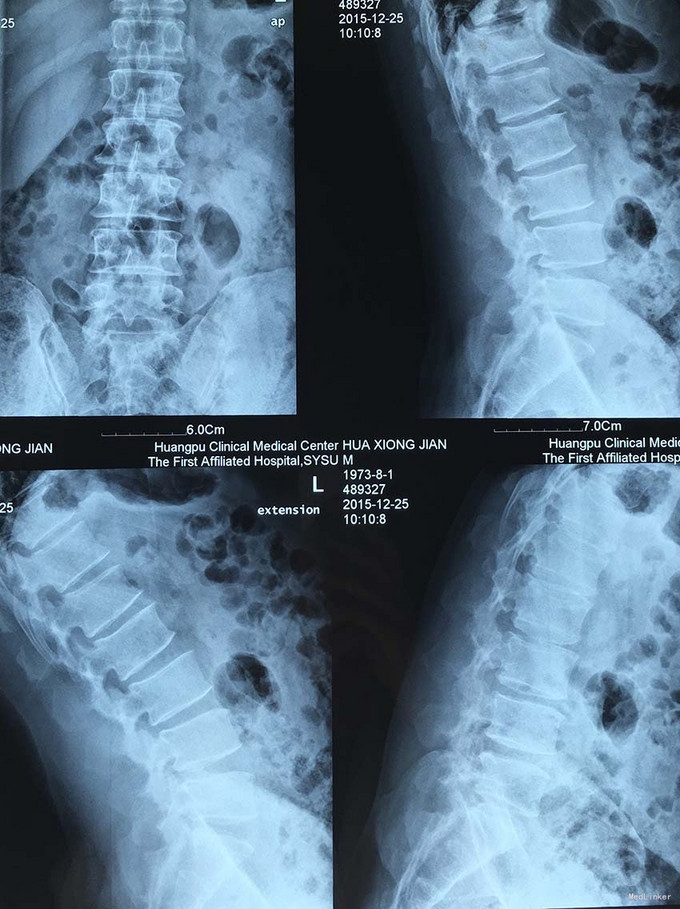

查体:脊柱生理弯曲存在,腰椎活动受限,L4/L5,L5/S1棘突压痛叩痛,叩击痛。左侧直腿抬高试验(+),约35°,加强试验(+),约30°。左下肢外侧皮肤感觉稍减退,右侧正常。双侧髂腰肌、股四头肌肌力Ⅴ级、左侧胫前肌、踇背伸肌肌力Ⅳ级,腹壁反射、肛门反射正常,两侧膝正常,双侧踝反射对称减弱。双侧Babinski征(-),双侧皮温及色泽正常,双侧足背动脉搏动良好。 辅助检查:腰椎磁共振检查显示:腰4/5椎间盘向左后方突出,压迫左侧神经根。骶管骶4水平发现一大小约2*3*3大小的囊肿。

诊断:1.腰4/5椎间盘突出症;2.骶管囊肿; 治疗:给予行左侧腰4/5椎板间开窗髓核摘除术。术后左腰臀部疼痛缓解明显,瞩其定期复查腰椎核磁共振。

随访:术后1个月随访,患者诉腰臀部疼痛明显缓解,左小腿麻木感减轻。 讨论:该患者术前椎间盘突出并不严重,而且合并骶囊肿,须仔细查体,明确责任病灶。骶管囊肿也可引起腰臀部疼痛不适感,术前须与患者交代清楚,手术摘除椎间盘有可能不能完全缓解症状,因骶管囊肿切除并发症较多,建议其随访观察。患者术后满意。